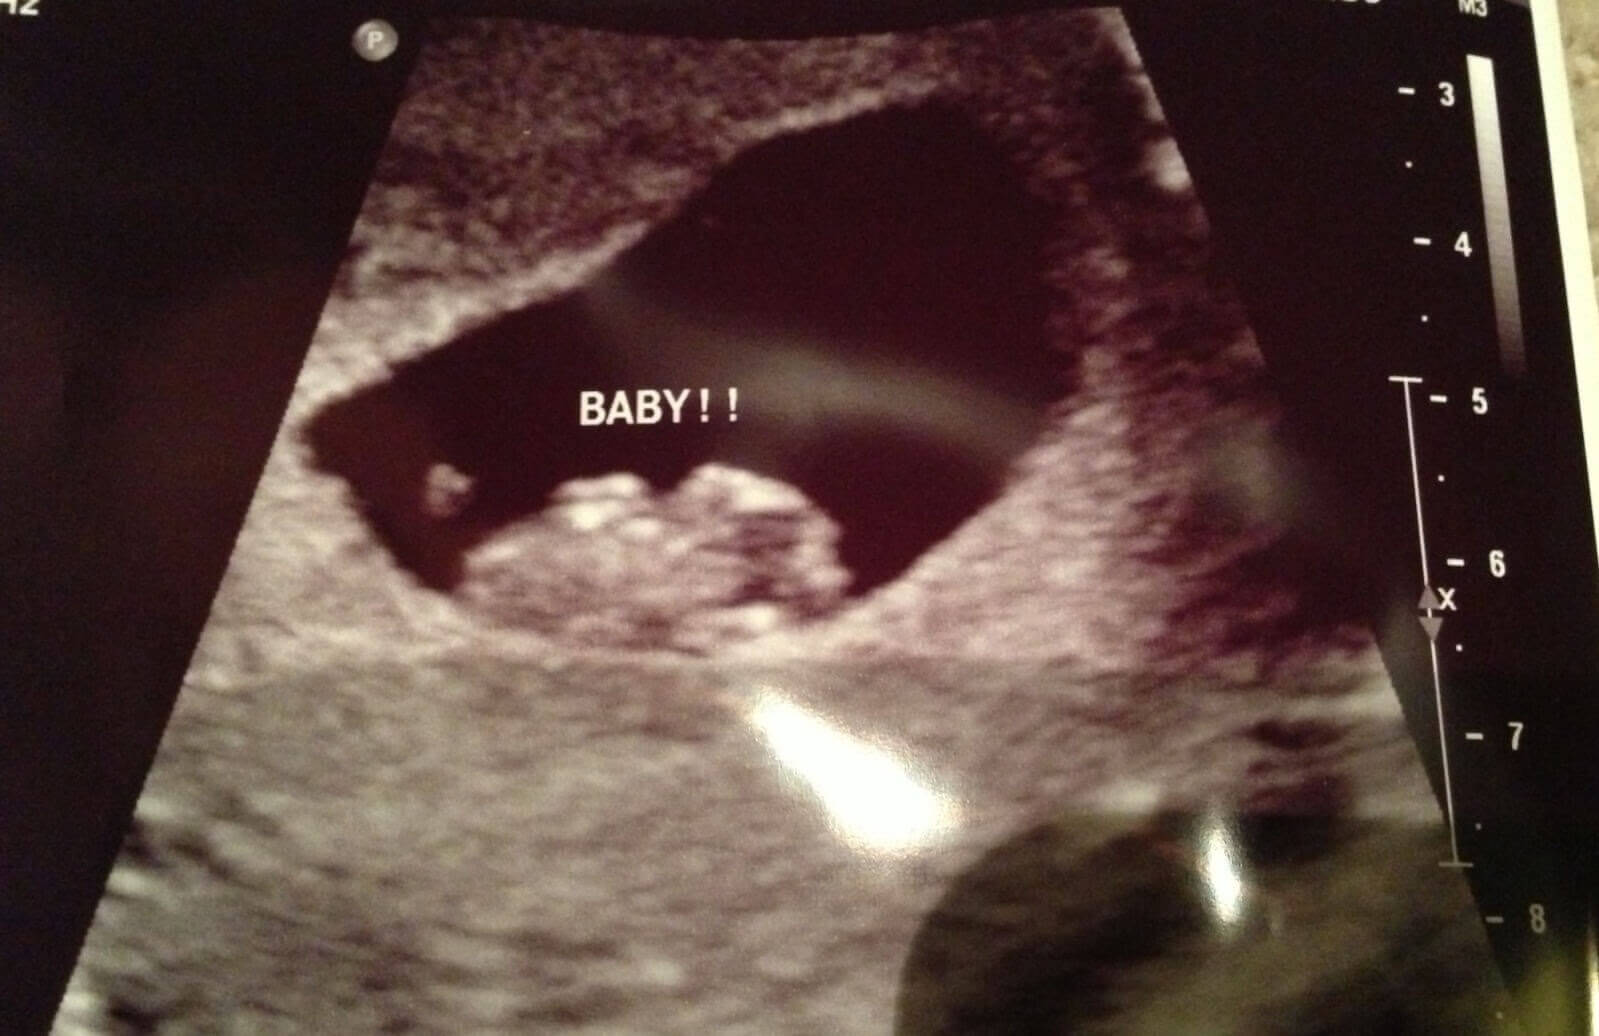

Fosterdiagnostik är avgörande för både dig och din bebis för att ni ska kunna gå igenom denna process på bästa sätt. Därför har vi samlat all den här goda informationen för dig gällande medcinska tester och hur du tar hand om dig själv i varje trimester. Varje mamma förtjänar en lycklig och hälsosam graviditet.